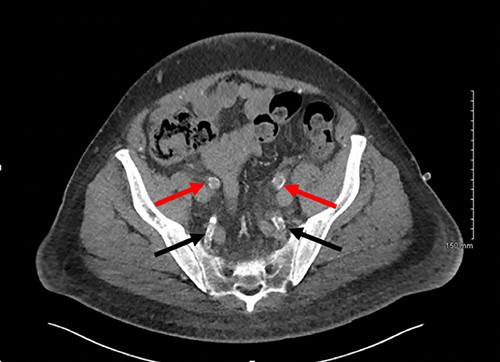

Axial slice of a non-contrast CT AP with red arrows showing calcified external iliac arteries and black arrows showing calcified internal iliac arteries.

Post-operatively the patient was experiencing ongoing severe penile, examination of the glans was not possible due to oedema and pain. Our patient underwent dialysis to offload excess fluid. A CT angiogram revealed extensive peripheral vascular arterial calcification, including calcification of the internal pudendal and cavernosal arteries (Figs 2 and 3). The inguinal lymphadenopathy was shown to be reactive.

The gold standard for the diagnosis remains skin biopsy. Biopsy of the foreskin at the time of dorsal slit did not elucidate any calciphylaxis, however did out rule malignancy. Glansectomy and circumcision confirmed calciphylaxis with vessel calcification and necrosis. However, often times diagnosis is made based on presentation, bloods and imaging, due to the risk of biopsy potentiating infection. Radiological investigations can aid diagnosis. CT is the most sensitive, assessing the extent of vascular calcification, as in our case [1] (Figs 2 and 3).